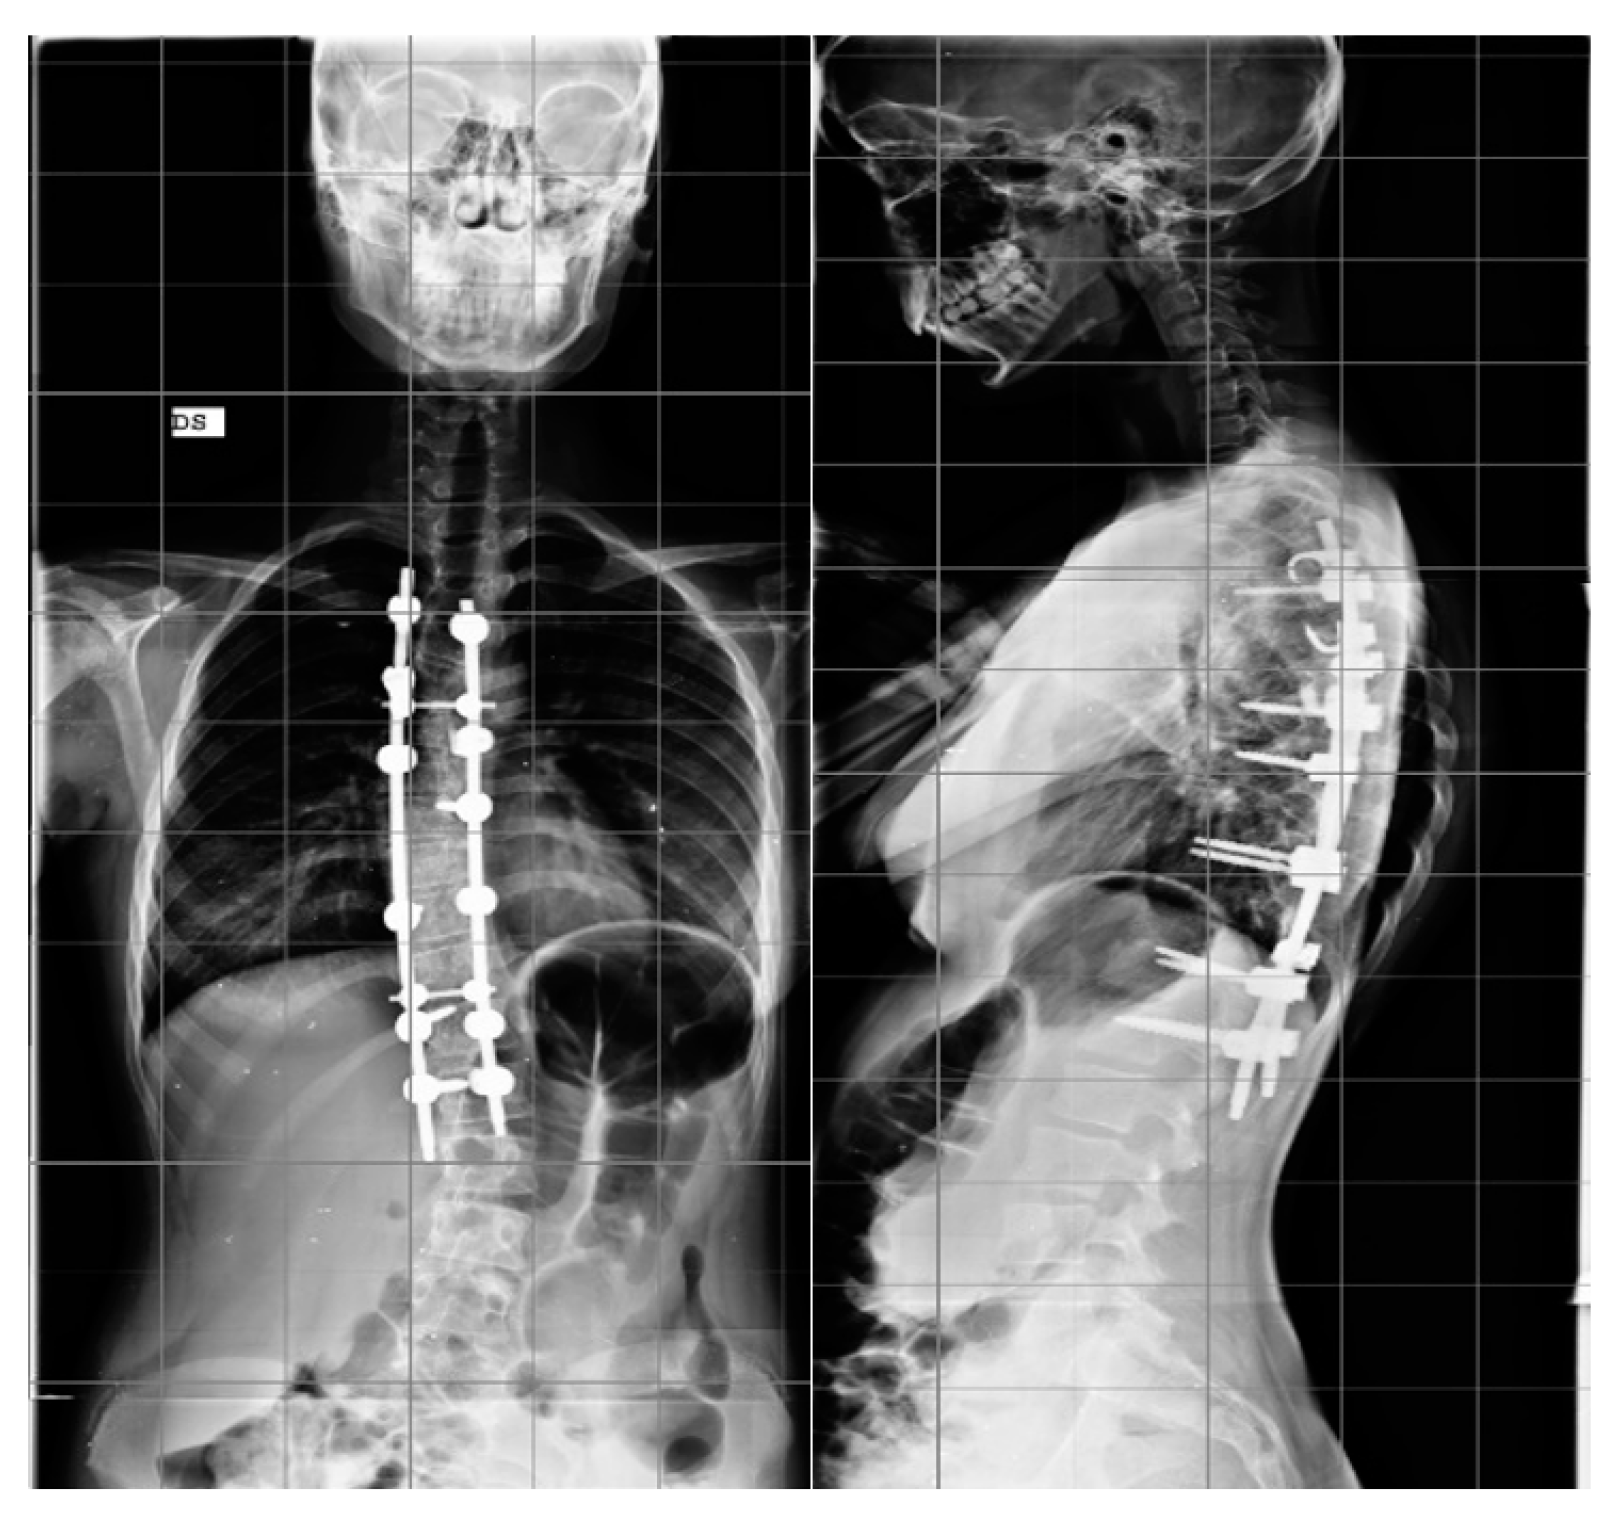

Step 2. Anchor point insertion: In the all-screw technique, titanium pedicel screws were inserted with the freehand technique with the assistance of C-arm fluoroscopy.(Figure 1).

Figure 1.

Example of all-pedicle screw construct for the treatment of AIS, AP, and LL.